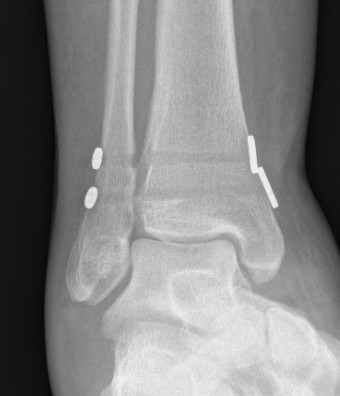

Unstable Weber B / torn deltoid ligament

Bimalleolar equivalent

Management

ORIF fibular

- ensure medial joint space fully reduced

- may need to open medial joint / removed osteochondral fragments / deltoid ligament

Open medial joint line after reduction

ORIF options

Plate - 1/3 tubular / DCP / anatomic locking plate

Fibular nail

ORIF